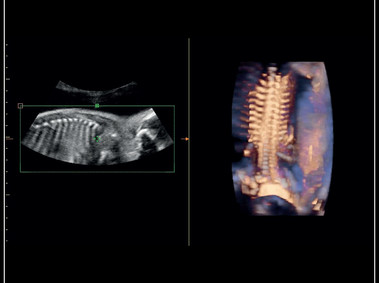

Giải pháp siêu âm sản phụ khoa toàn diện với chế độ 3D/4D và công nghệ X-light – bố trí nguồn sáng và làm mịn da mặt em bé